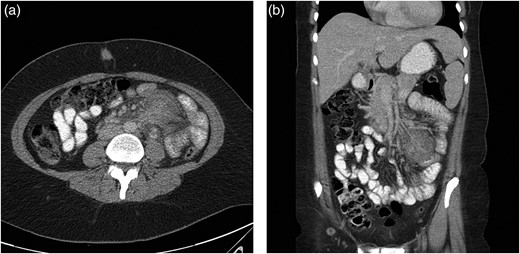

An ultrasound of the abdomen revealed a tumourous mass in the left lower quadrant of the abdomen. On computed tomography (CT) scan and MRI this appeared to be a tumour in the radix mesenterii (Fig. 1a and b). The differential diagnosis included neoplastic processes, such as malignant lymphoma, desmoid tumour, a carcinoid or a gastro-intestinal stromal cell tumour.

(a) Transverse CT image with the ill-defined tumour in the left side of the patient. (b) Coronal CT image showing the same ill-defined tumour.